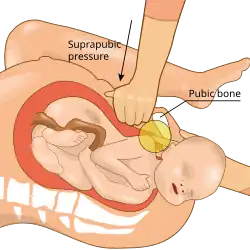

| Suprapubic pressure being used in a shoulder dystocia | |

- Pressure: Suprapubic pressure

- McRoberts maneuver; it is usually the first maneuver performed as it is easy, noninvasive, and effective.[11] It involves hyperflexing the mother's legs tightly to her abdomen. This widens the pelvis, and flattens the spine in the lower back (lumbar spine).[18] This maneuver is usually combined with applying suprapubic pressure or Rubin I by having an assistant apply pressure above the pubic bone with the palm or fist, directing the pressure on the anterior shoulder both downward (to below the pubic bone) and laterally (toward the fetus's face or sternum).[11] Together, McRoberts maneuver and suprapubic pressure relieves about 58% of shoulder dystocias.[19]